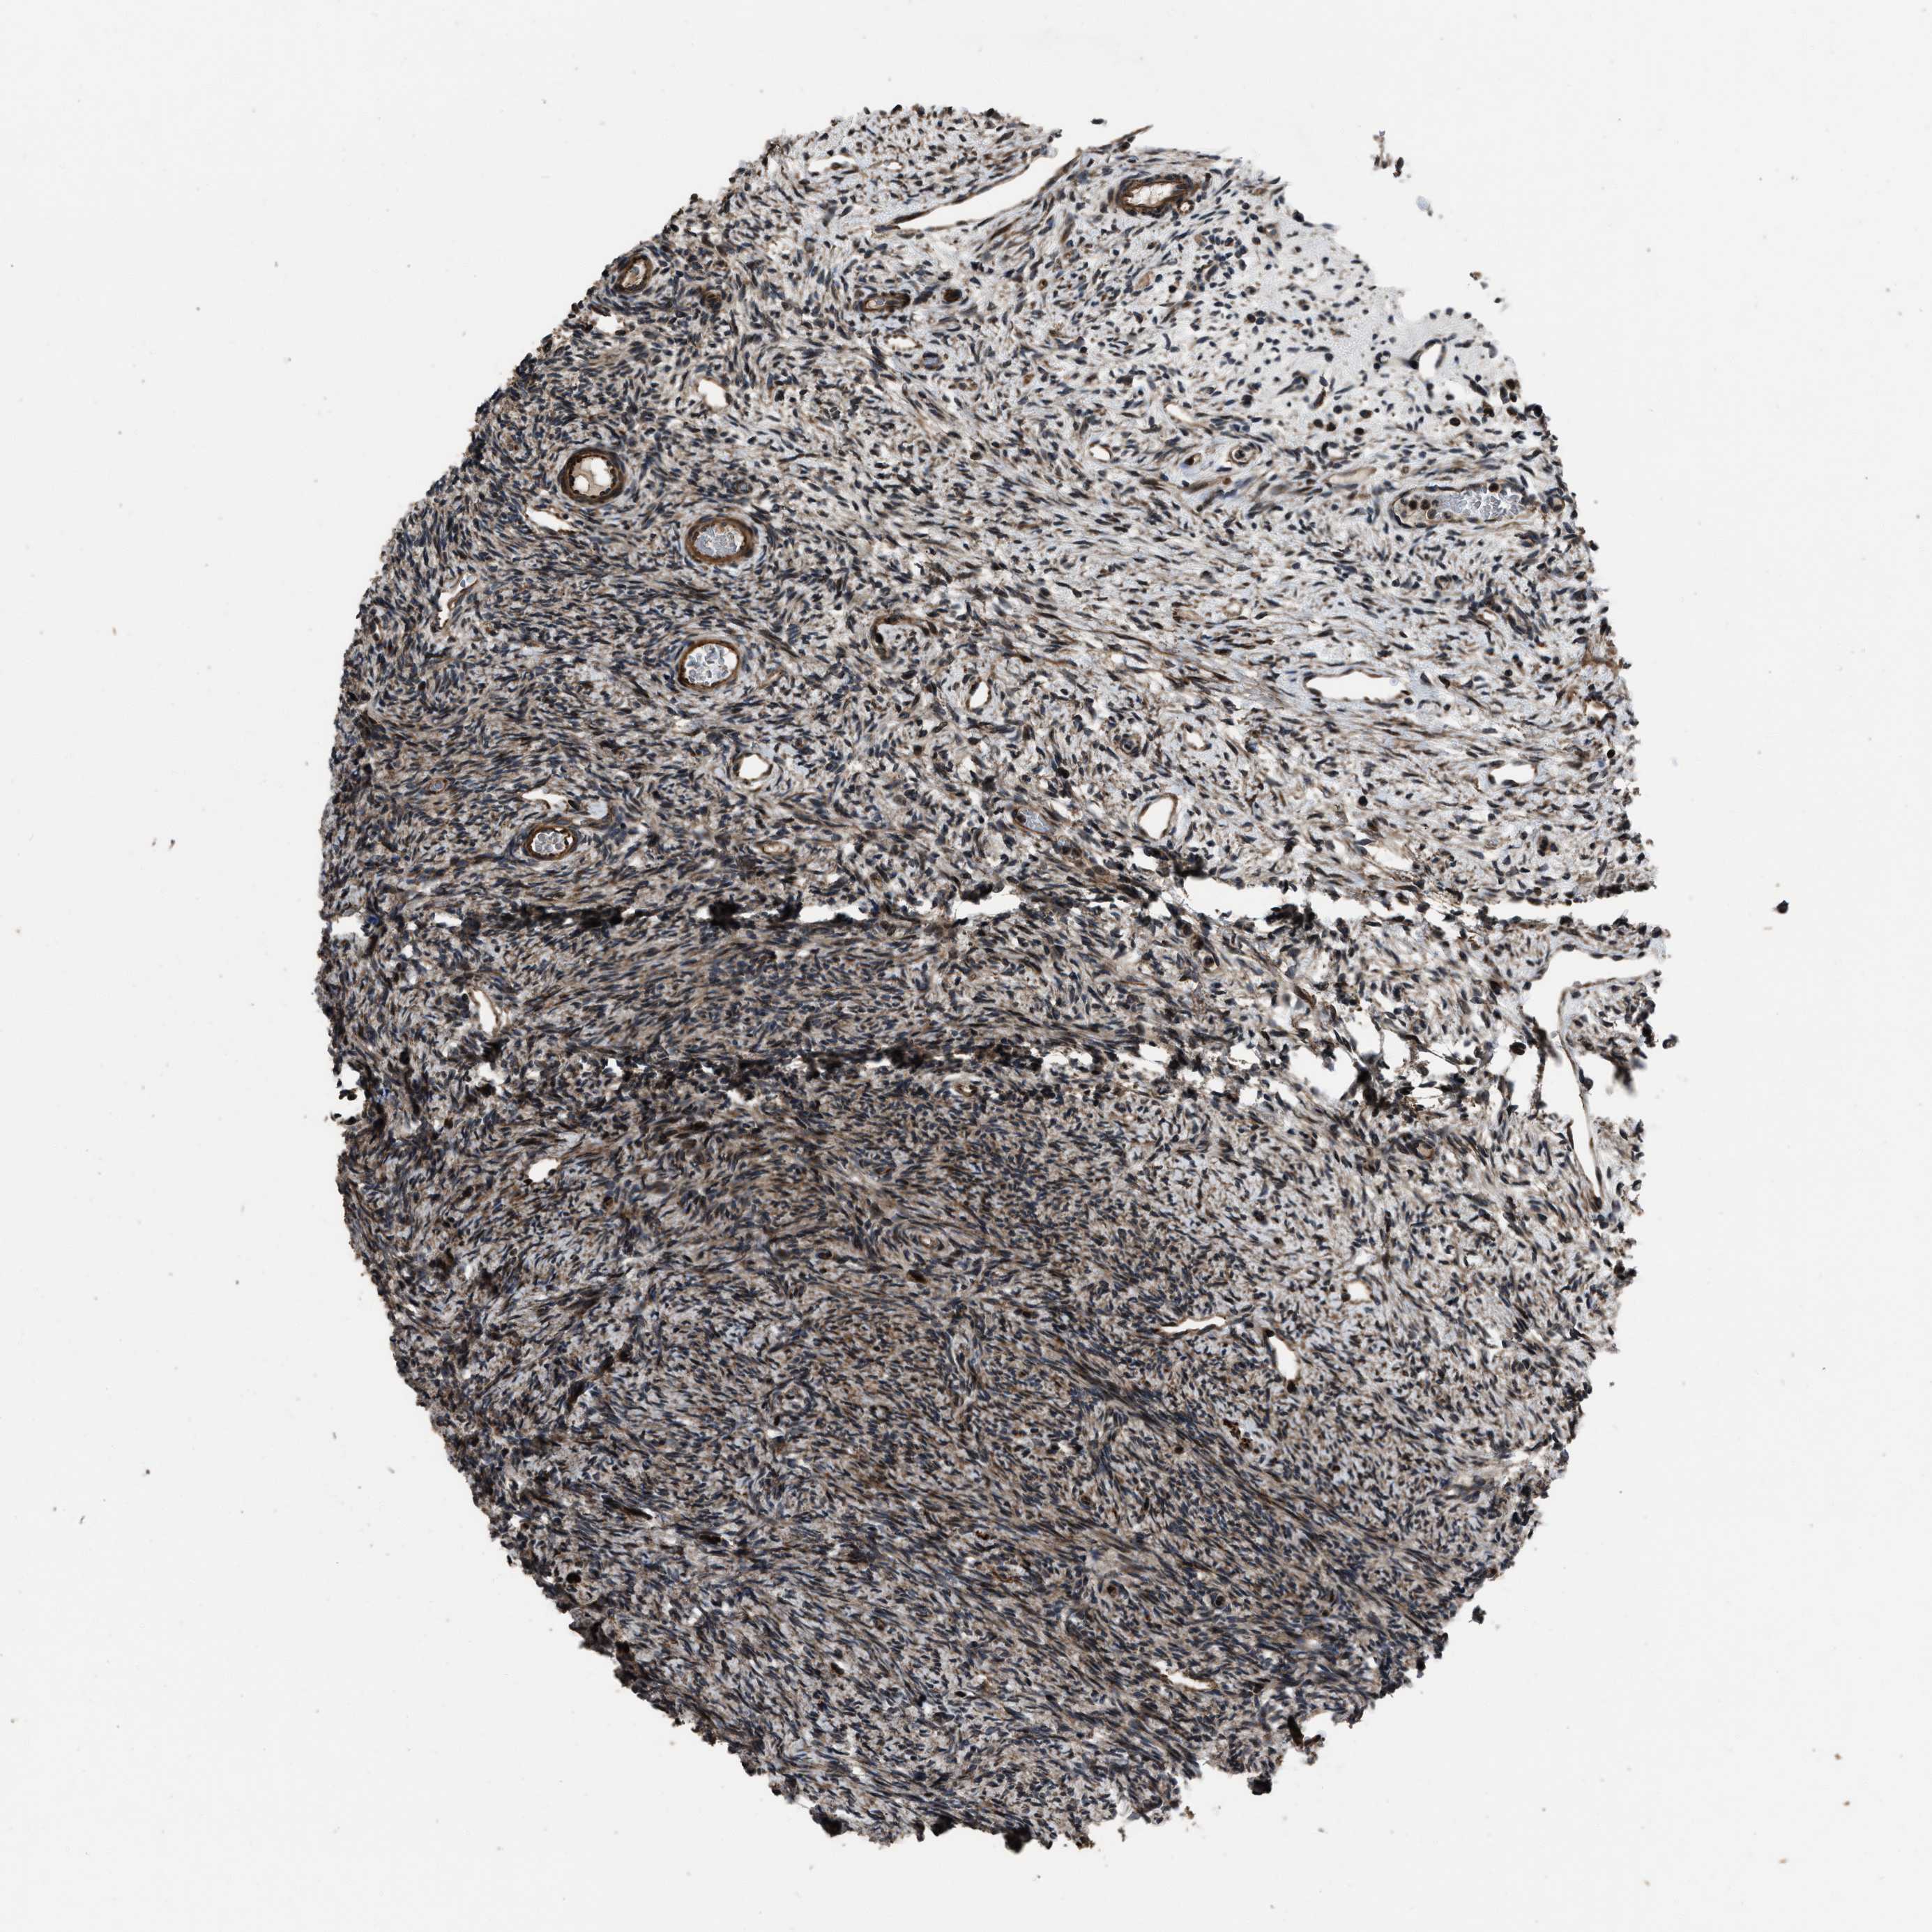

NSD3